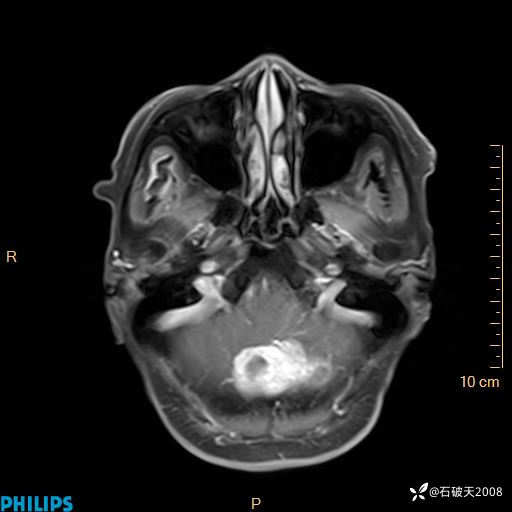

书上说这个肿瘤发生在幕下仅4.09%,你会想到它吗?(病理已公布)

女 86岁 主 诉:乏力1月

现病史:患者1月前活动出现双下肢乏力,无头晕、头痛、恶心、呕吐、肢体活动不利,休息后缓解,间断断发作,症状进行性加重,在家口服药物治疗(具体不详),效差,为进一步诊治,来我院,门诊按“乏力”收住我科,患者自发病以来,神志清,精神稍差,饮食睡眠欠佳,大小便正常,体重未见明显改变。

T2